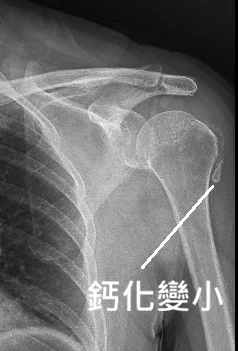

- 肩部問題(鈣化性肌腱炎、五十肩、旋轉肌病變): 臨床研究表明,震波能有效擊碎深層鈣化。2003 年的單盲試驗顯示,高達 71% 的患者在治療後出現鈣化點的完全吸收 (31%) 或部分吸收 (40%) [3];2024 年發表的最新文獻進一步分析了影響肩部鈣化沉積物吸收的因素,證實震波做為免開刀選項的高可靠性 [7]。2024 年《Frontiers in Medicine》系統性回顧亦確認,震波對旋轉肌腱炎的止痛效果在 3 個月與 6 個月追蹤時均顯著優於安慰劑 [10]。

👉 醫學實證解析:雖然震波治療成功挽救了許多患者免於開刀,但它並非萬靈丹。根據 2024 年的研究 [7],鈣化點的吸收率與鈣化的質地(如 Gärtner 分類中的柔軟度)、大小及病程時間有關。對於處於急性發炎期、液化中的極大鈣化,或是合併嚴重肌腱全層撕裂的患者,有時仍需由醫師評估是否採用超音波導引抽吸 (Barbotage) 或微創手術介入。